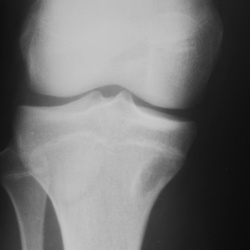

Пациентка жалуется на боль в обл. внутр. мыщелка б.берц кости. Снимки мерзкого качества, но это все, что есть, временной интервал - около года (9 - 10 гг). Прилагаю КТ на пленке. Наша версия -...